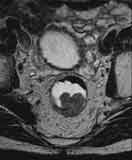

| T2-gew. axial mit rektaler Füllung |

T2-gew. axial mit rektaler Füllung |

pT3-Rektumkarzinom mit Infiltration in die Subserosa |